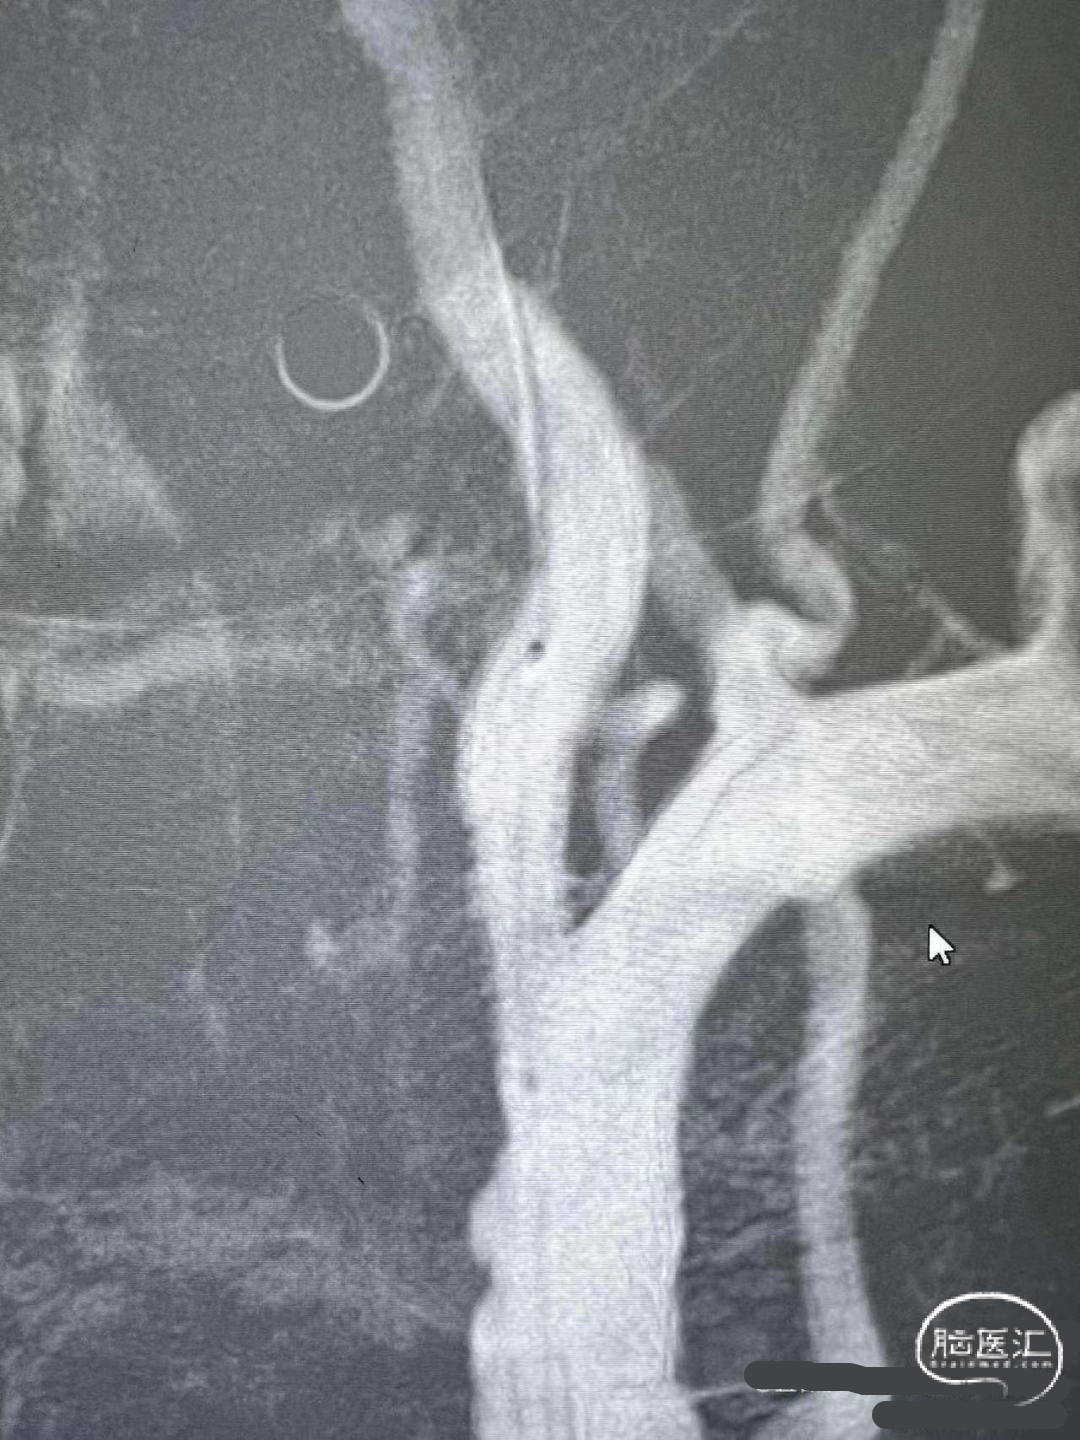

术前DSA影像

右侧颈内动脉起始部中度狭窄,未见血流向后循环代偿。

左侧颈内动脉造影提示后交通开放,代偿供应后循环。

左侧椎动脉开口重度狭窄,前向血流缓慢,V4闭塞。